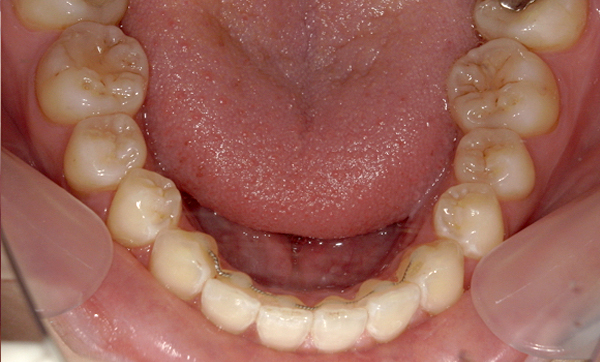

症例_009 「上下の前歯」症例

治療期間:7ヶ月金額:54万円+税20代女性捻転歯一部の反対咬合前歯のガタガタ